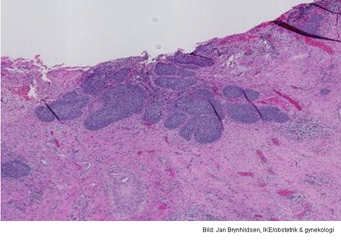

Vad visar bilden?

A

Cervixcancer

Q

Invasivt växande skivepitelcancer.